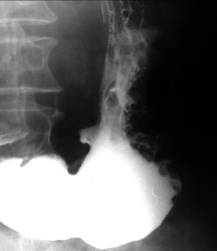

Stomacul este dilatat si prezinta unde peristaltice adânci, frecvente, ineficiente. Evacuarea este încetinita. Canalul piloric este îngustat alungit de 1-2 cm, având aspect de pilor în paranteze sprijinite, de pilor între paranteze când muschiul piloric protrude în baza bulbului duodenal sau în antru, sau pilor în duble paranteze.